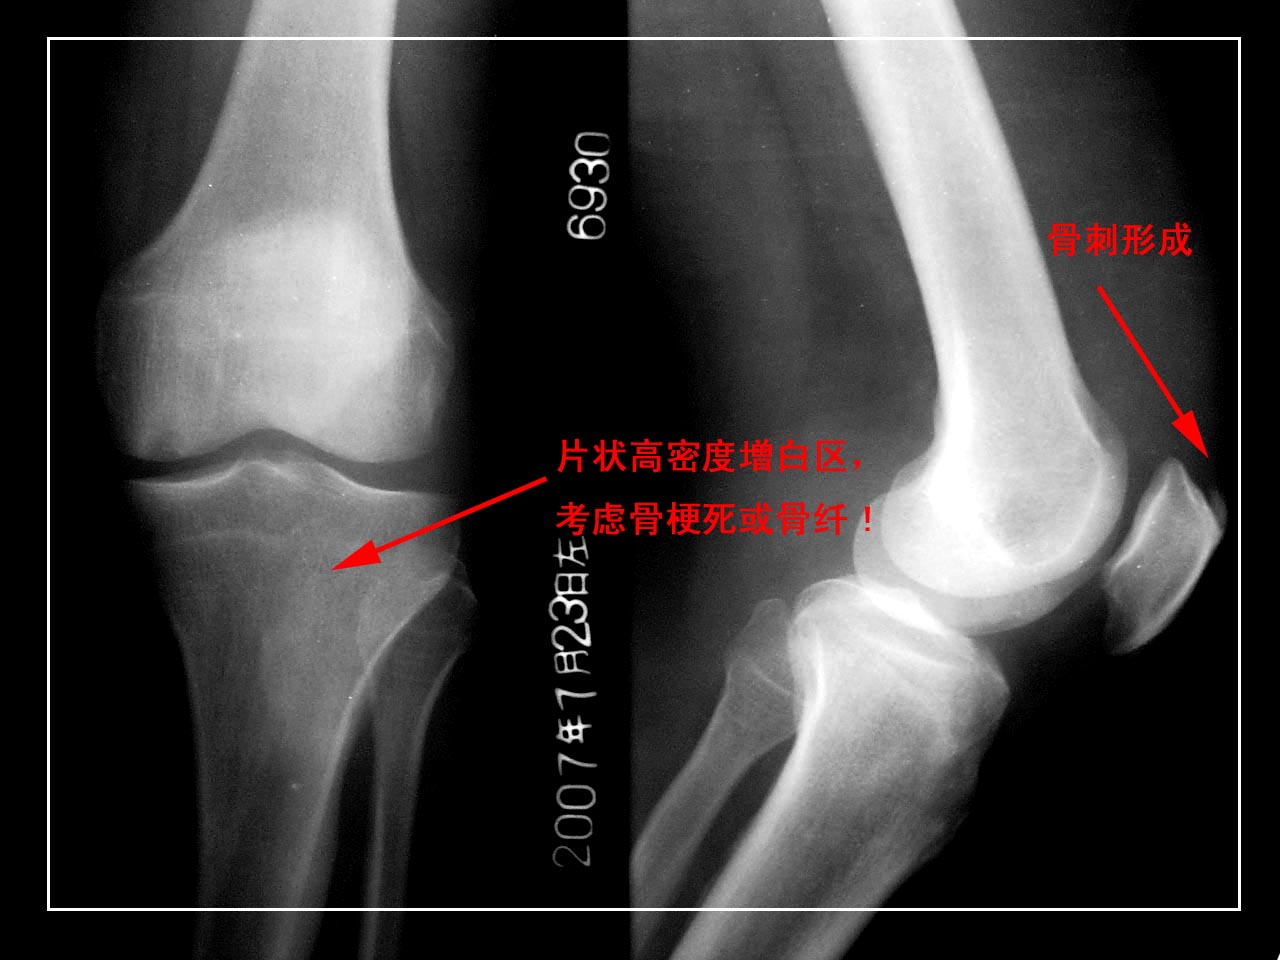

男,65岁,左膝关节痛疼半年,软组织稍肿,活动尚可。

1髌骨前上缘骨刺。

1.左股四头肌肌腱钙化;

2.左股骨内侧髁下(关节面)局限性骨质密度减低区,性质?加上关节软组织肿胀,最好作进一步检查(mri)。

左髌骨前上方股四头肌]韧带钙化。

左股骨下内侧髁剥脱性骨炎。

考虑:1、左侧股骨内髁剥脱性骨软骨炎;

2、髌骨前上缘骨刺。

1、左髌骨前上方股四头肌]韧带钙化。

2、左股骨下内侧髁剥脱性骨炎。